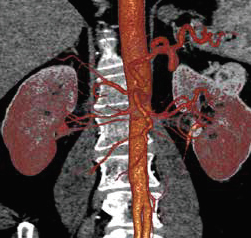

CT Excellence in:

Vascular Imaging

Exams we offer include : Run-offs, Dissection, Stent Planning & Evaluation, Pre-& Post-Carotid Surgery and CT Angiography